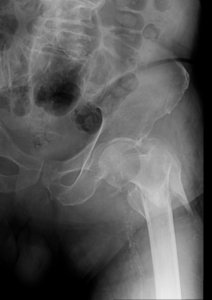

- Hip Fractures.